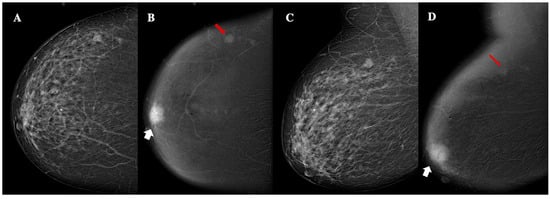

Figure 4.

Contrast-enhanced mammography of a 63-year-old patient with BI-RADS 5 lesion. Panel (A,C) show a low-energy MLO view, highlighting dense breast parenchyma. Panel (B,D) display the corresponding recombined image, revealing a 24 mm oval lesion with non-circumscribed margins, heterogeneous enhancement, high conspicuity (white arrows), and an additional 8 mm oval lesion with circumscribed margins, homogeneous enhancement, and low conspicuity (red arrows). These findings are consistent with unilateral, multifocal, grade 3, triple-negative ductal cancer, with lymphovascular invasion.